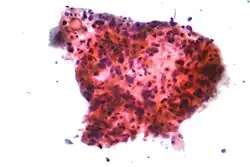

O câncer de pulmão é classificado de acordo com o tipo histológico.[51] Essa classificação tem implicações importantes no manejo clínico e no prognóstico da doença. A vasta maioria dos tumores de pulmão é do tipo carcinoma - doença maligna derivada de células epiteliais. Os carcinomas de pulmão são categorizados pelo tamanho e aparência das células malignas observadas no tecido de biópsia por um patologista em um microscópio. As duas classes gerais são carcinomas não pequenas células e pequenas células.[52]

Carcinoma não pequenas células

Os carcinomas de pulmão não pequenas células (CNPC) são reunidos num único grupo porque seus prognósticos e manejos são similares. Existem três subtipos principais: adenocarcinoma, carcinoma de pulmão de células escamosas e de grandes células.

Aproximadamente 40% dos tumores de pulmão são adenocarcinomas. Esse tipo de câncer é geralmente originado no tecido pulmonar periférico.[51] A maioria dos casos de adenocarcinoma está associada ao tabagismo; contudo, entre pessoas que fumaram menos de 100 cigarros em toda a vida (nunca fumaram),[7] o adenocarcinoma é a forma mais comum de câncer de pulmão.[53] Um subtipo de adenocarcinoma, o carcinoma bronquíolo-alveolar, é mais comum em mulheres que nunca fumaram e pode apresentar respostas diferentes ao tratamento.[54]

O carcinoma de células escamosas, também conhecido como epidermoide ou espinocelular, corresponde a cerca de 30% dos tumores de pulmão. Ele, tipicamente, ocorre na porção mais central do órgão, nas proximidades das vias aéreas. Uma cavidade oca e necrose associada são frequentemente encontradas no centro do tumor.[51]